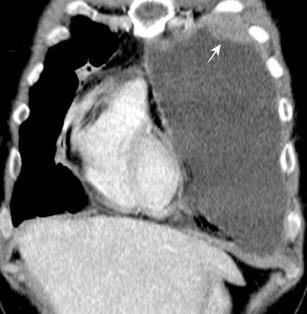

La ocupación del espacio pleural por derrame (o obstrucción aérea) se acomoda con expansión aumentada de la caja torácica, especialmente en eje vertical. La consecuencia es aplanamiento e incluso inversión diafragmática.

Afzal S, Fatima K, Ambareen M. Antenatal ultrasound diagnosis of congenital high airway obstruction syndrome: a case report and review of literature. Cureus. 2019. Thoma R et al. Physiology of breathlessness associated with pleural effusions. Curr Opin Pulm Med. 2015

Wang JS et al. Changes in pulmonary mechanics and gas exchange after thoracentesis on patients with inversion of a hemidiaphragm secondary to large pleural effusion . Chest 1995

Mesotelioma epitelioide